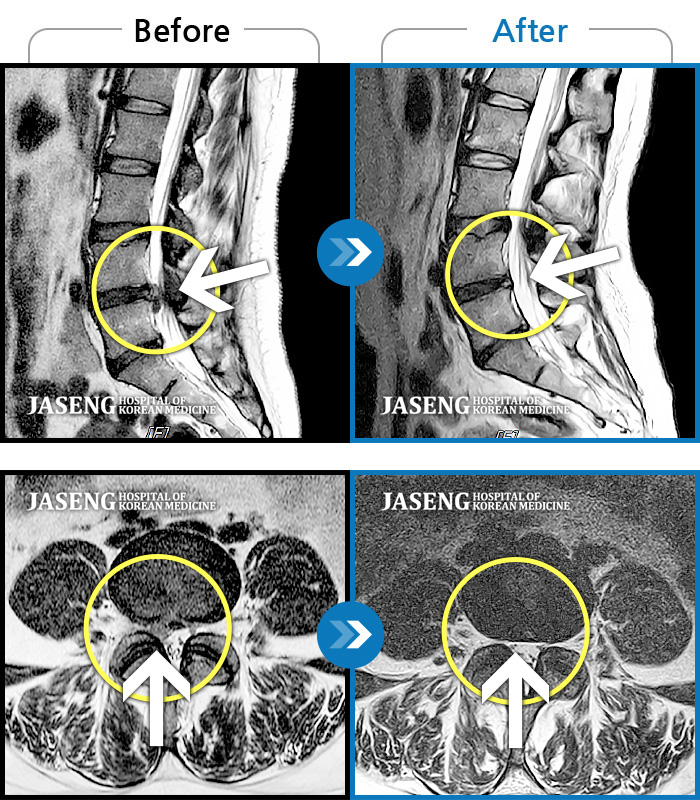

허리디스크

강남 · 강만호 원장

운동하다 삐끗한 후 허리디스크가 터지고 흘러올라가 극심한 통증을 호소하셨습니다.

촬영시기

2021.04.04 ~ 2023.05.10

2023.06.16

조회수 169